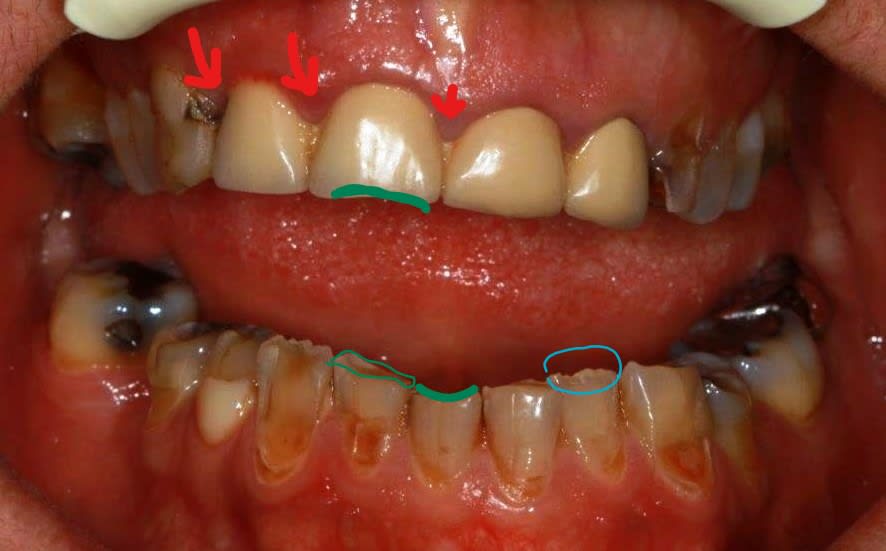

Je reprends le fil de départ:

- la patiente voudrait sourire: ok

-la patiente voudrait manger :?????? (je ne vois pas ce qui l'empeche, malgré un articulé inversé coté gauche qu'elle a toujours eu

Sans orthodontie, orthopédie, et peut etre chirurgie, je ne vois pas de solutions fiables pour annuler cet inversé qui correspond a un décalage squelettique tres important.

Le risque majeur en bidouillant les axes des protheses (qui peteront les racines...) est de créeer des douleurs d'atm en forcant la retrusion mandibulaire coté gauche.

Je sui persuadé que pxav va refaire des jolies ceramiques (ca , c'est sur) .... en conservant cet inversé d'articulé....

Franchement si c'est pour garder l'inversé et le bloc antérieur...je ne vois pas l’intérêt de ce cas, non je vais essayer de modifier tout ça , sans ortho, juste provisoire et dans la foulée ceram d'usage...